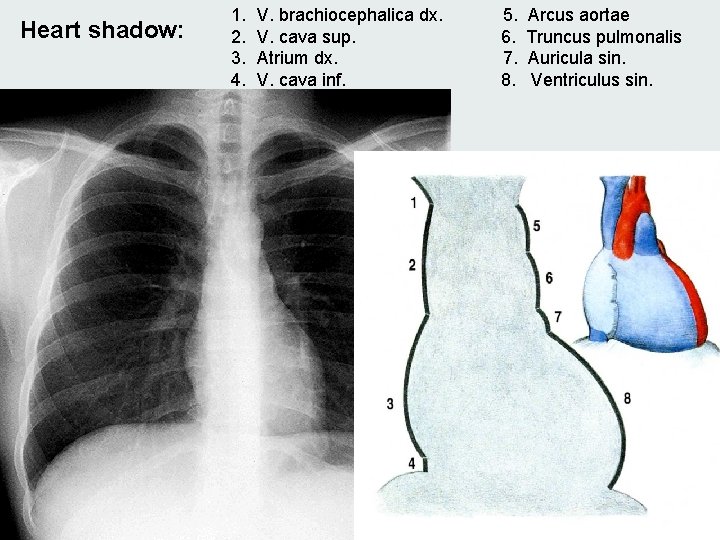

Heart shadow: 1. 2. 3. 4. V. brachiocephalica dx. V. cava sup. Atrium dx. V. cava inf. 5. 6. 7. 8. Arcus aortae Truncus pulmonalis Auricula sin. Ventriculus sin.

Distantia mediodextra Distantia mediosinistra Transverse line = DMd+DMs Length Gradient Area